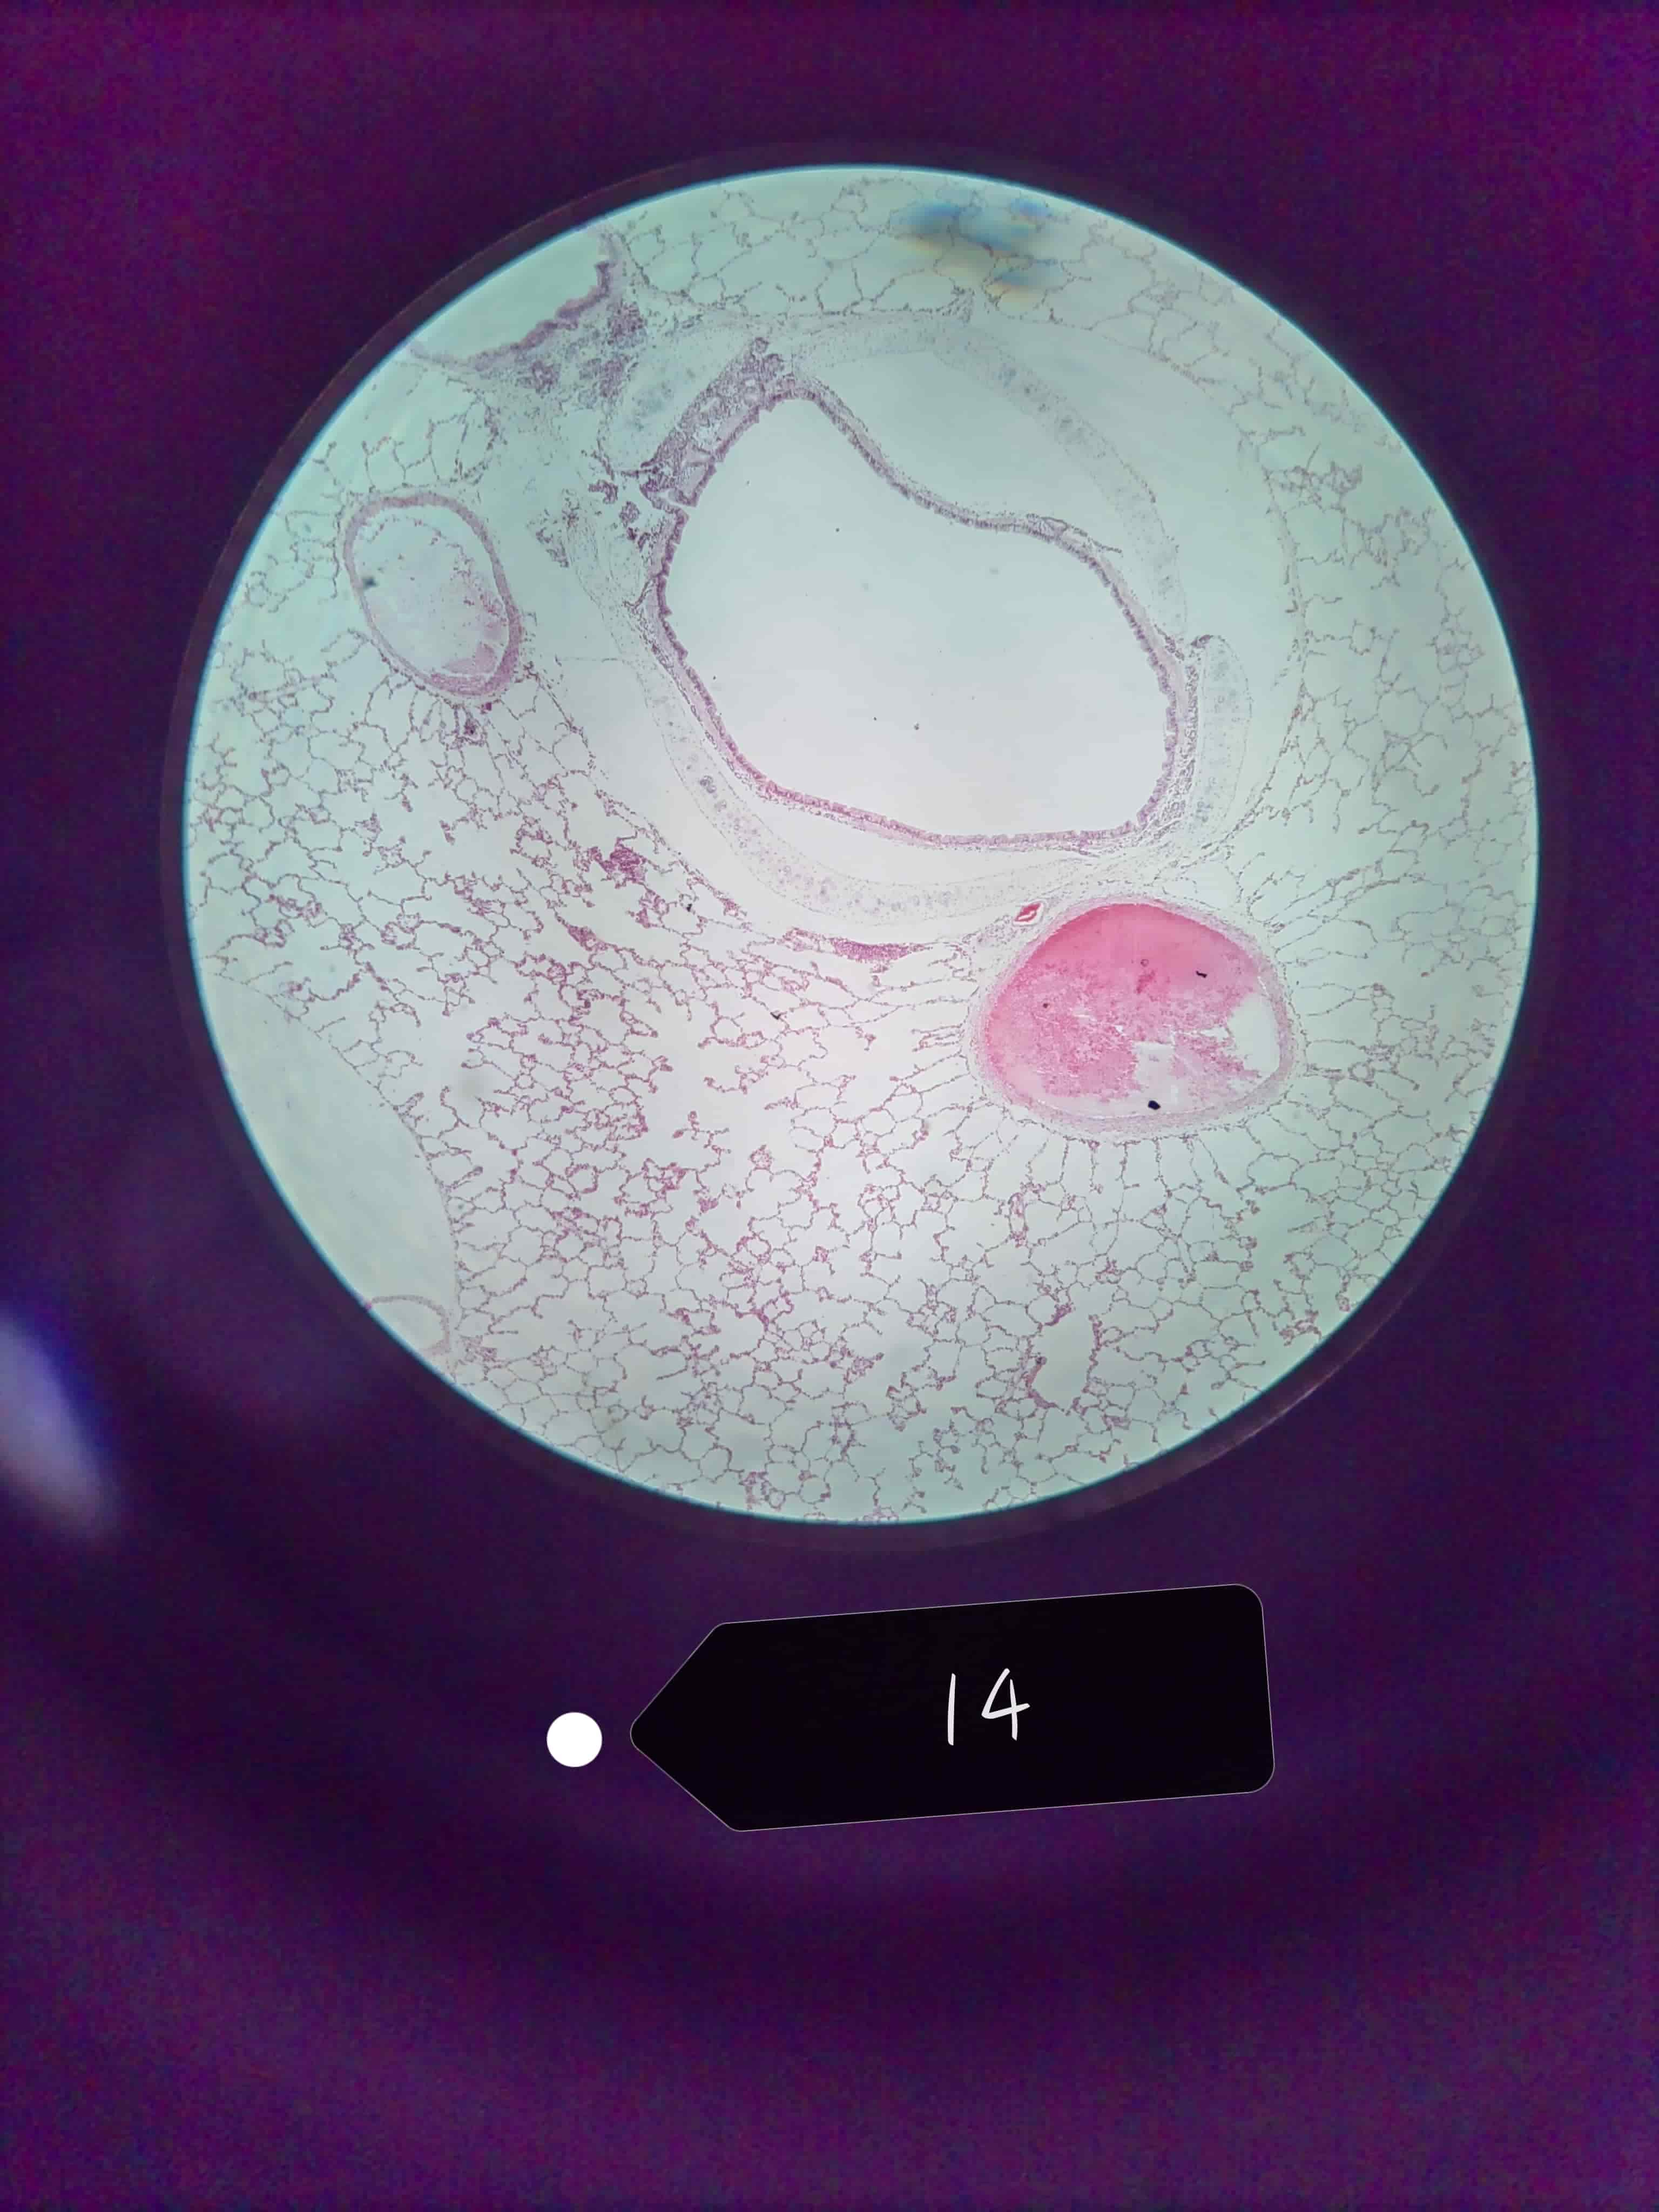

肺

肺泡

细支气管